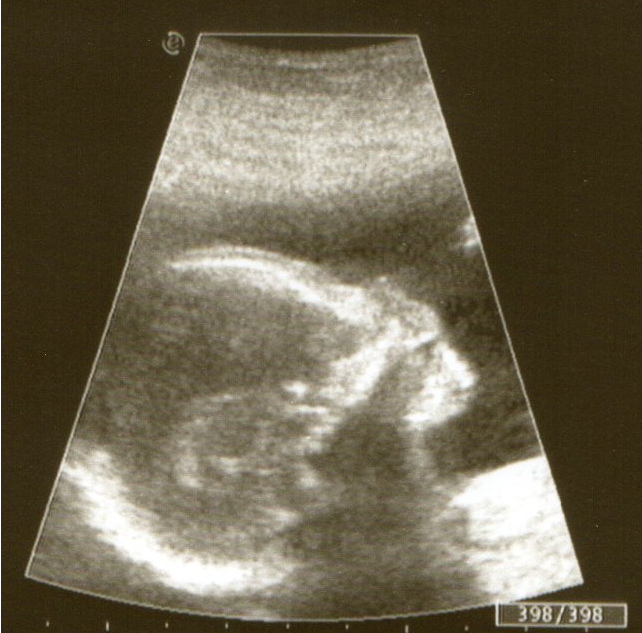

это наша голова...видно носик, глазки, ротик